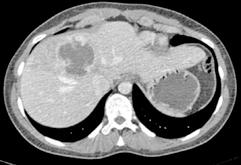

Figura 4.

TC realizado tras las dos embolizaciones arteriales. Vemos cómo la lesión ha disminuido considerablemente de tamaño y ahora está más alejada de las VSH y de la cava. Esto permite la ligadura de las VSH en su confluencia con la cava. Inicialmente no habría sido posible por su cercanía y tamaño.